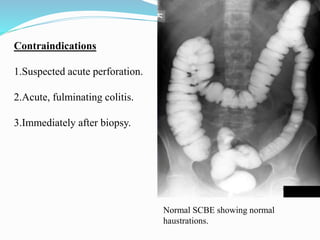

This document discusses colorectal polyps. It defines polyps and describes their types, including neoplastic and non-neoplastic polyps. It discusses adenomatous polyps in depth, noting their malignant potential increases with size over 1cm and villous architecture. Radiological diagnostic methods for polyps including single and double contrast barium enema and CT colonography are explained. The document provides an overview of polyp pathogenesis and genetic syndromes like FAP that increase cancer risk.